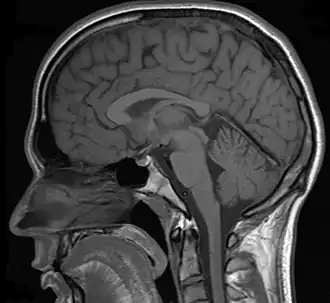

In a case of misdiagnosed depression recounted in Newsweek, a writer received treatment for depression for years; during the last 10 years of her depression the symptoms worsened, resulting in multiple suicide attempts and psychiatric hospitalizations. When an MRI finally was performed, it showed the presence of a tumor. However, she was told by a neurologist that it was benign. After a worsening of symptoms, and upon the second opinion of another neurologist, the tumor was removed. After the surgery, she no longer had depressive symptoms.[28]

CNS Tumors

In addition to pituitary tumors, tumors in various locations in the central nervous system may cause depressive symptoms and be misdiagnosed as depression.[28][69]